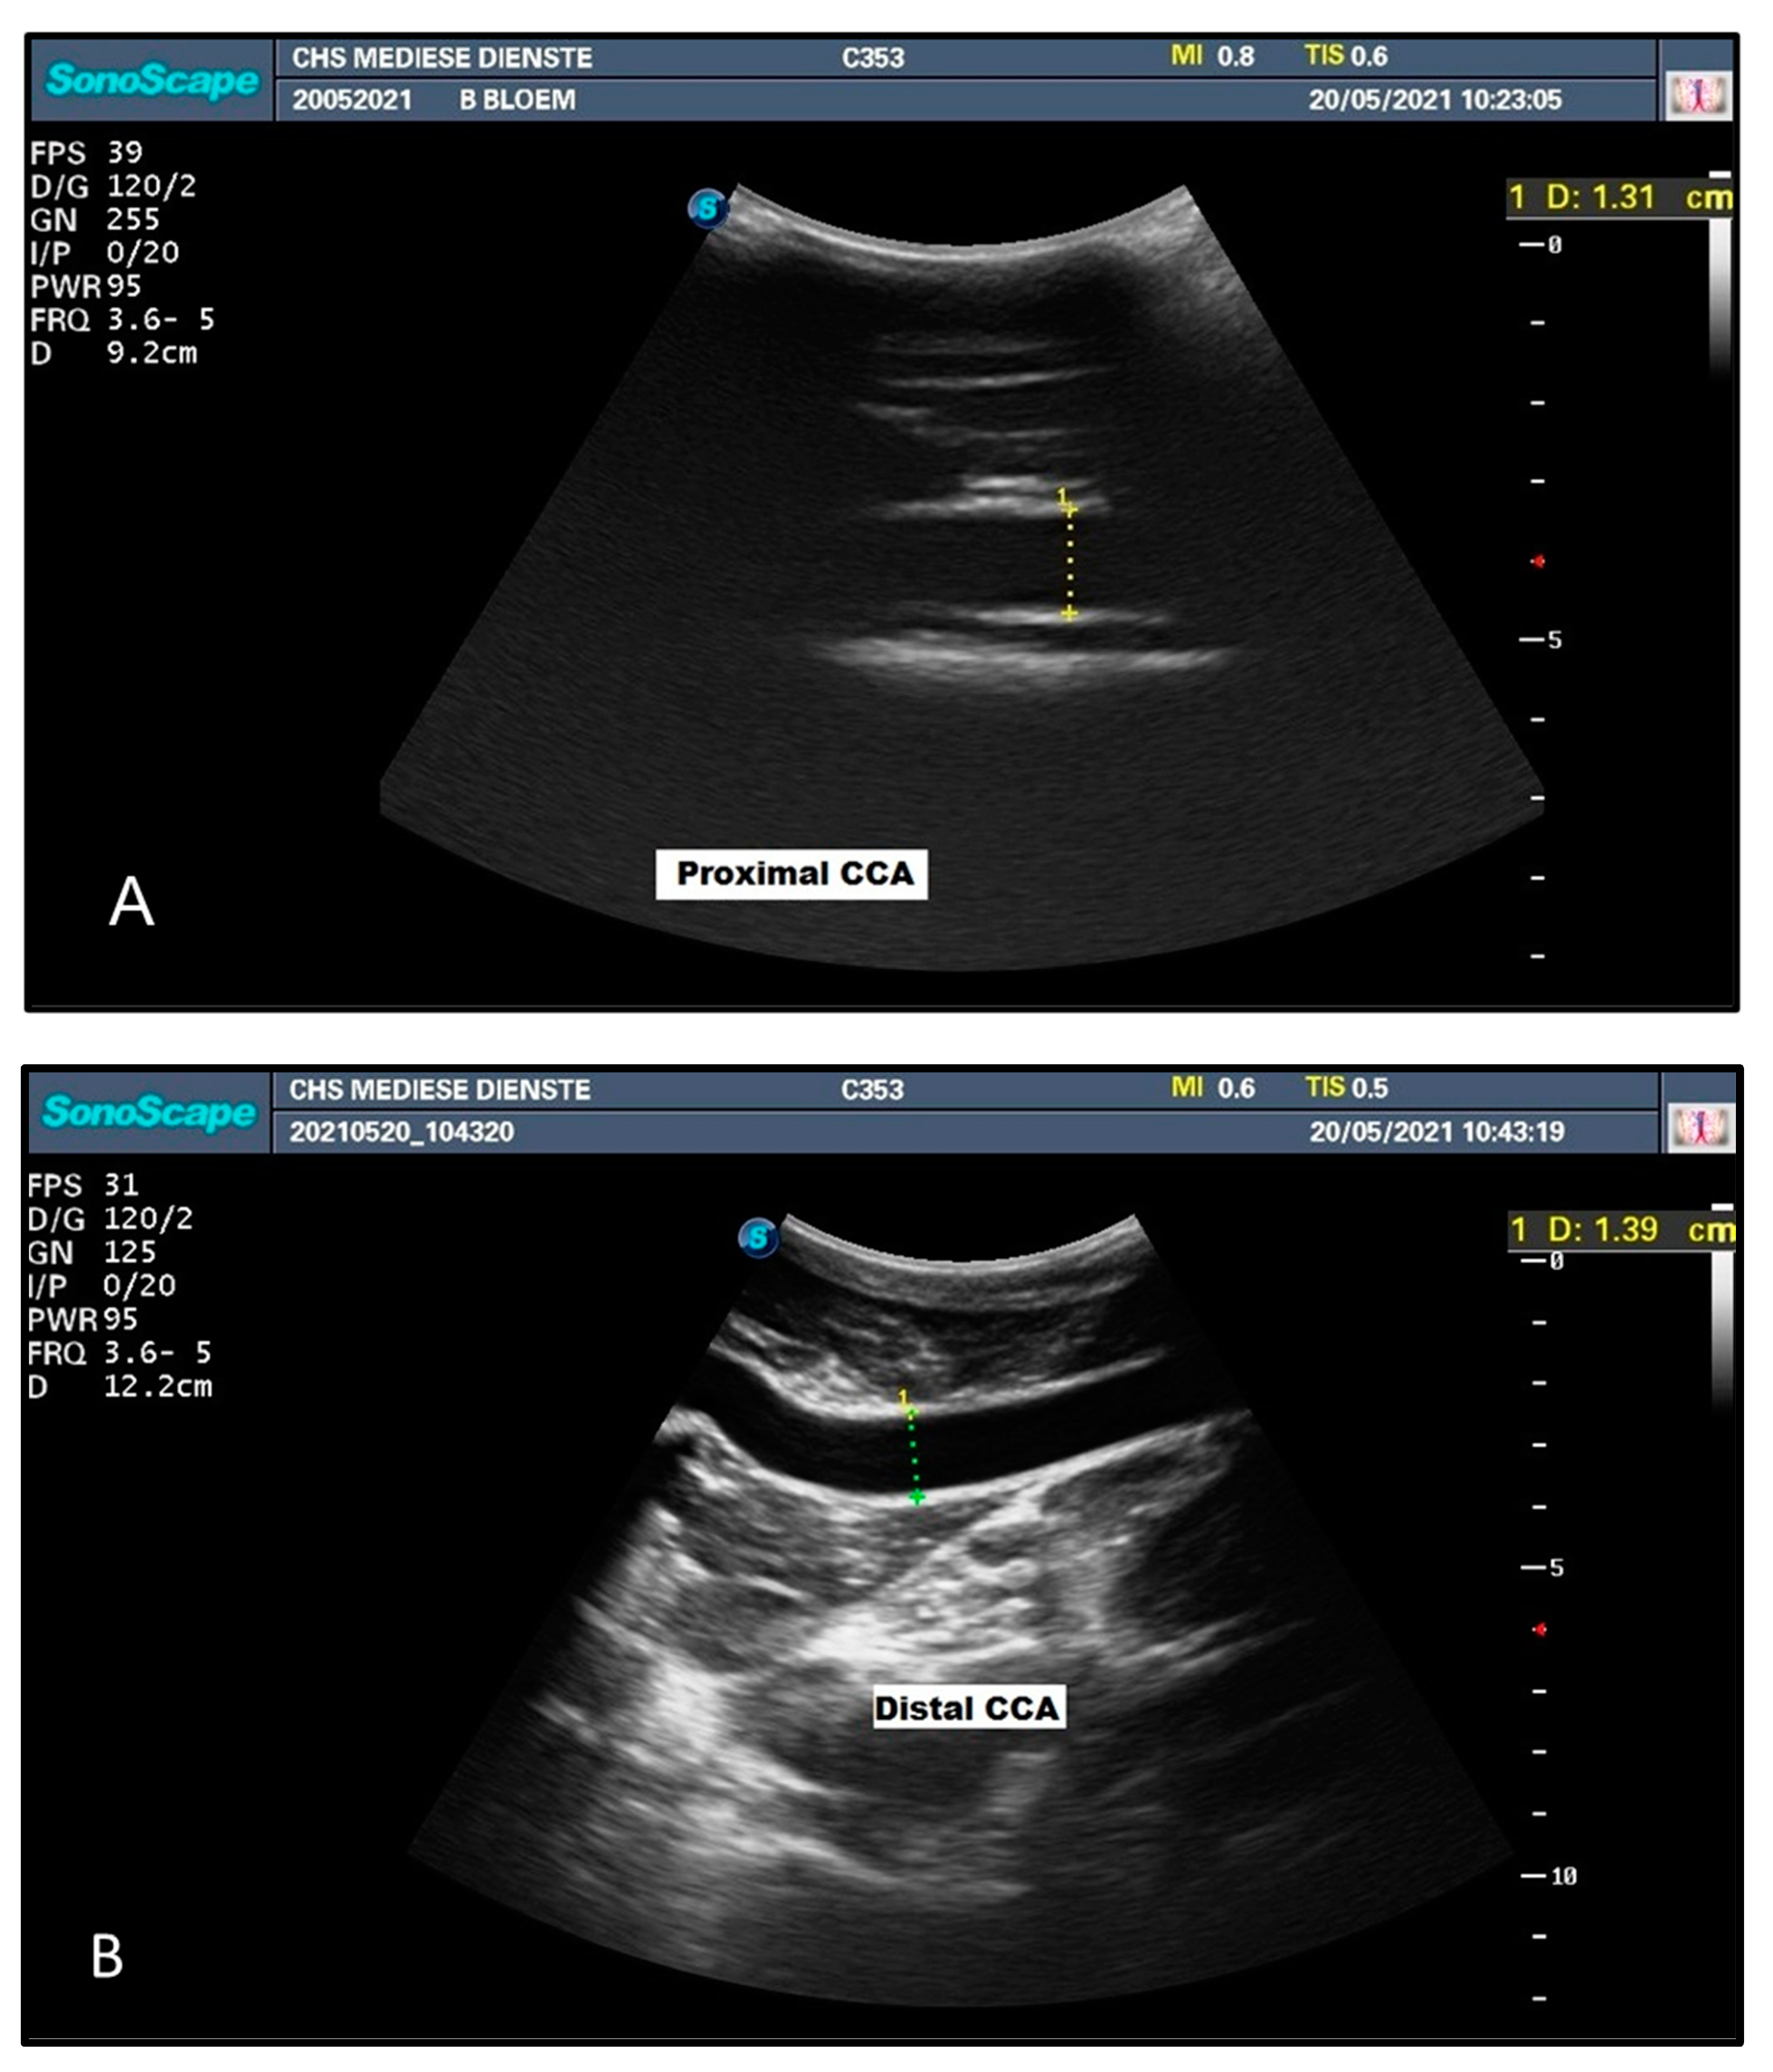

| Head Position | Diameter (mm) CCA | Diameter (mm) IJV | ||

|---|---|---|---|---|

| Proximal | Distal | Proximal | Distal | |

| Head Up | 13.8 | 13.9 | 4.6 | 13.9 |

| Head Down | 13.1 | 13.3 | 12.6 | 16.1 |